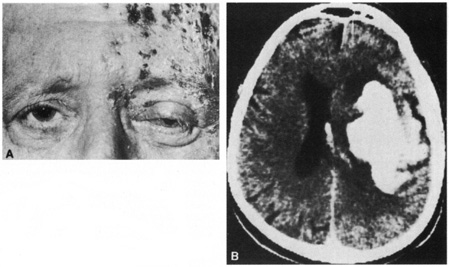

and angiography. Neurology 31:1030, 1981 45. NcNeil JD, Horowitz M: Contralateral hemiplegia complicating herpes zoster ophthalmicus. J R Soc Med 84:501, 1991 46. Severson EA, Baratz KH, Hodge DO, et al: Herpes zoster ophthalmicus in Olmsted County, Minnesota: have systemic